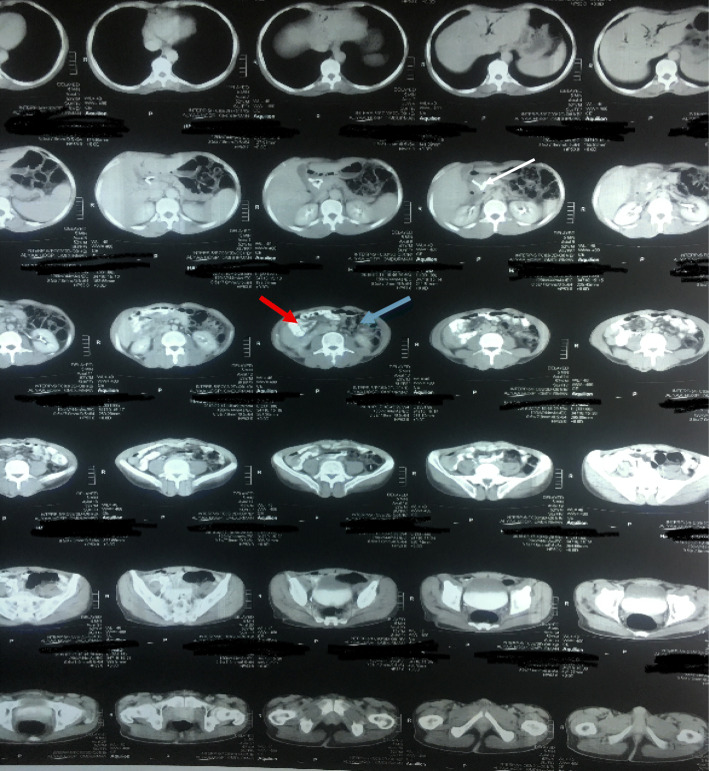

Fig. 1.

Computed tomographic scan of the abdomen showing malrotation of the bowel, periampullary mass, dilated common bile duct, and stent inside (white arrow), small bowel on the Right side (red arrow) and large bowel on the left (blue arrow)

Fig. 2.

Computed tomographic scan of the abdomen showing inversion of superior mesenteric artery (red arrow) and superior mesenteric vein (blue arrow)